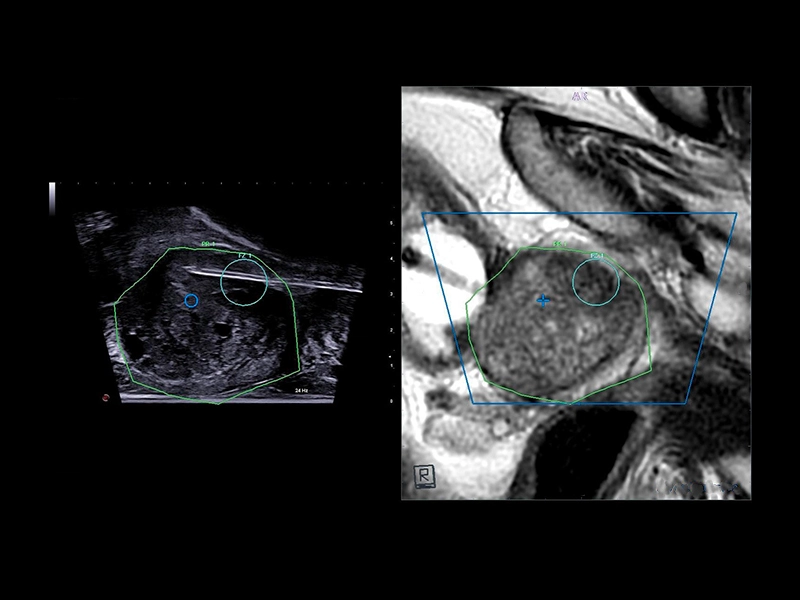

MyLab™E80 - Urofusion - TP Biopsy

MyLab™E80 - Urofusion - TP Biopsy